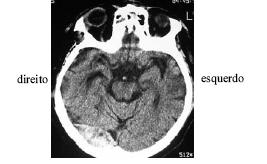

Enunciado 267966-1

Após ter sofrido queda de um cavalo, um senhor de 55 anos de idade foi levado imediatamente ao pronto-socorro, onde se verificou, além das escoriações no corpo, pequeno hematoma subgaleal em região temporoparietoccipital direita. Foi medicado com analgésicos e antiemético. Após vinte minutos, os sintomas foram aliviados e o paciente solicitou alta hospitalar. O clínico geral solicitou o parecer do neurologista visto que os socorristas relataram perda de consciência, fato negado pelo paciente. Passadas 4 horas do trauma, o paciente mostravase inquieto, mas negava cefaléia ou náuseas. Foi levado para realização de tomografia computadorizada, cujo resultado é mostrado na figura acima. Na presença do neurologista, o paciente solicitou alta hospitalar, informando que morava a apenas 25 km do hospital e voltaria se houvesse piora. Diante de situação como a apresentada, após analisar o exame de imagem e o caso clínico, o neurologista deve